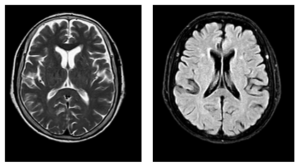

CASE LÂM SÀNG: ĐIỀU TRỊ BỆNH NHÂN MẮC HAI LOẠI UNG THƯ: UNG THƯ HẮC TỐ TÁI PHÁT DI CĂN VÀ UNG THƯ BIỂU MÔ TẾ BÀO GAN TẠI TRUNG TÂM Y HỌC HẠT NHÂN VÀ UNG BƯỚU, BỆNH VIỆN BẠCH MAI.

CASE LÂM SÀNG: ĐIỀU TRỊ BỆNH NHÂN MẮC HAI LOẠI UNG THƯ: UNG THƯ HẮC TỐ TÁI PHÁT DI CĂN VÀ UNG THƯ BIỂU MÔ TẾ BÀO GAN TẠI TRUNG TÂM Y HỌC HẠT NHÂN VÀ UNG BƯỚU, BỆNH VIỆN BẠCH MAI. GS.TS. Mai Trọng Khoa, BSNT. Nguyễn Văn Tiến,...